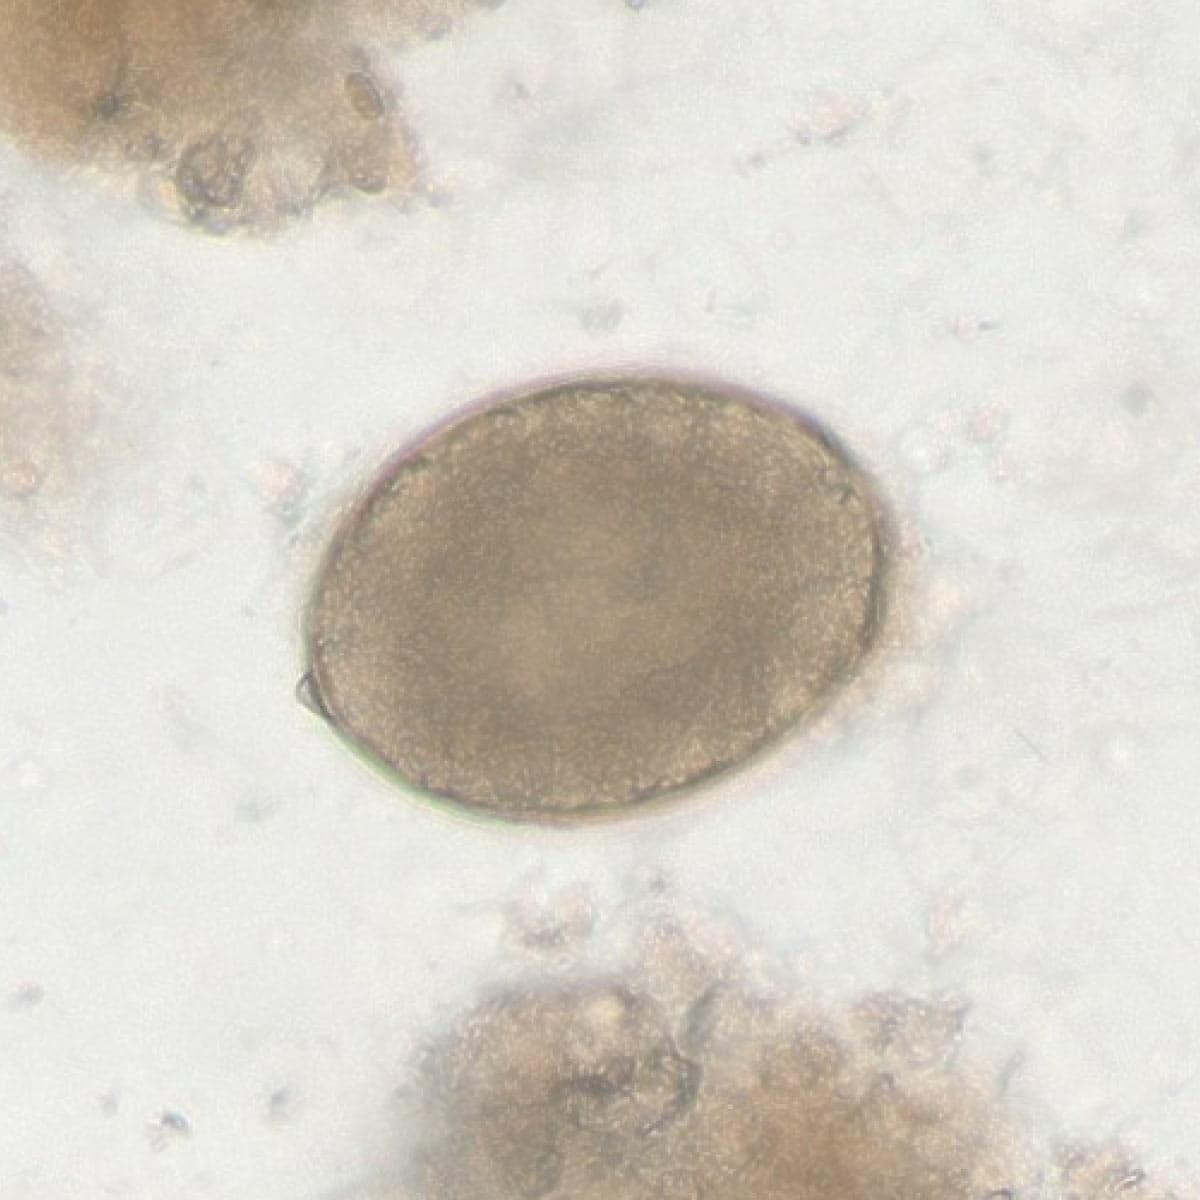

Automatic detection over 30 species

Built on worldwide parasite-positive specimens, ParaScout AI identifies a vast number of parasite species, including those that are clinically rare or challenging to find.